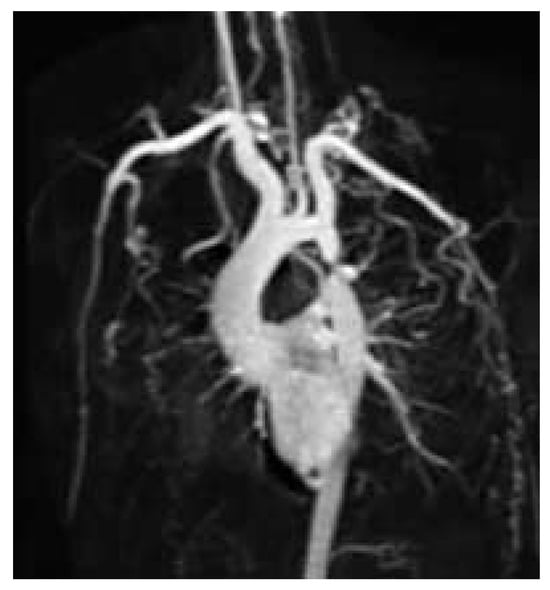

Figure 1. Left ventricle with apical thinning and apical / periapical trabeculations.

The chest radiograph showed no abnormality. The ECG at rest did not show left ventricular hypertrophy nor any other abnormality. However, on clinical examination, there was no palpable pulse in the lower extremities. The echocardiogram revealed the expected stenosis of the descending aorta with a peak gradient of 62 mm Hg. The left ventricle was not dilated (60 mm), but showed apical thinning (4.4 mm) and trabeculations with local hypokinesia. There was no valvular abnormality such as eg a bicuspid aortic valve, but a slight aortic root dilation (40 mm) was detected.

A cardiovascular magnetic resonance study (CMR) was performed at our institution in order to assess the exact location, the degree and severity of the aortic stenosis and to rule out associated congenital anomalies. CMR showed a normal left ventricular mass (181 g, 95.3 g/m2, [normal: 91 ± 11 g/m2]), a moderately reduced left ventricular ejection fraction of 37.6%, a diffuse, apically pronounced hypokinesia with apical trabeculations (fig. 1), and no late contrast enhancement. In CMR, the aortic root was slightly dilatated (40 mm), the ascending aorta was normal but the aortic arch was slightly hypoplastic. The proximal part of the descending aorta showed a severe postductal stenosis (fig. 2) of 28 mm in length, a small poststenotic saccular aneurysm (confirmed by surgery, fig. 3), and an extensive collateral vascular system through the subclavian, scapular, internal thoracic, and intercostal arteries. The origin and proximal course of the coronary arteries as well as the pulmonary venous return were normal.

In unusual presentation as in our case including virtual absence of symptoms, an only mild hypertension, a normal ECG at rest, and a normal chest radiograph, the diagnosis is difficult and can be easily missed. However, the absence of the pulse in the lower limbs reveals the “pulseless disease”. The additional findings in our patient included a left ventricular dysfunction, apical thinning and increased trabeculations, which may, however, also be due to an unknown coincidence with a form of cardiomyopathy, to hypertension, or due to an association of the coarctation with non compacted myocardium. This latter association has been published in a series of 12 patients with ventricular noncompaction [].